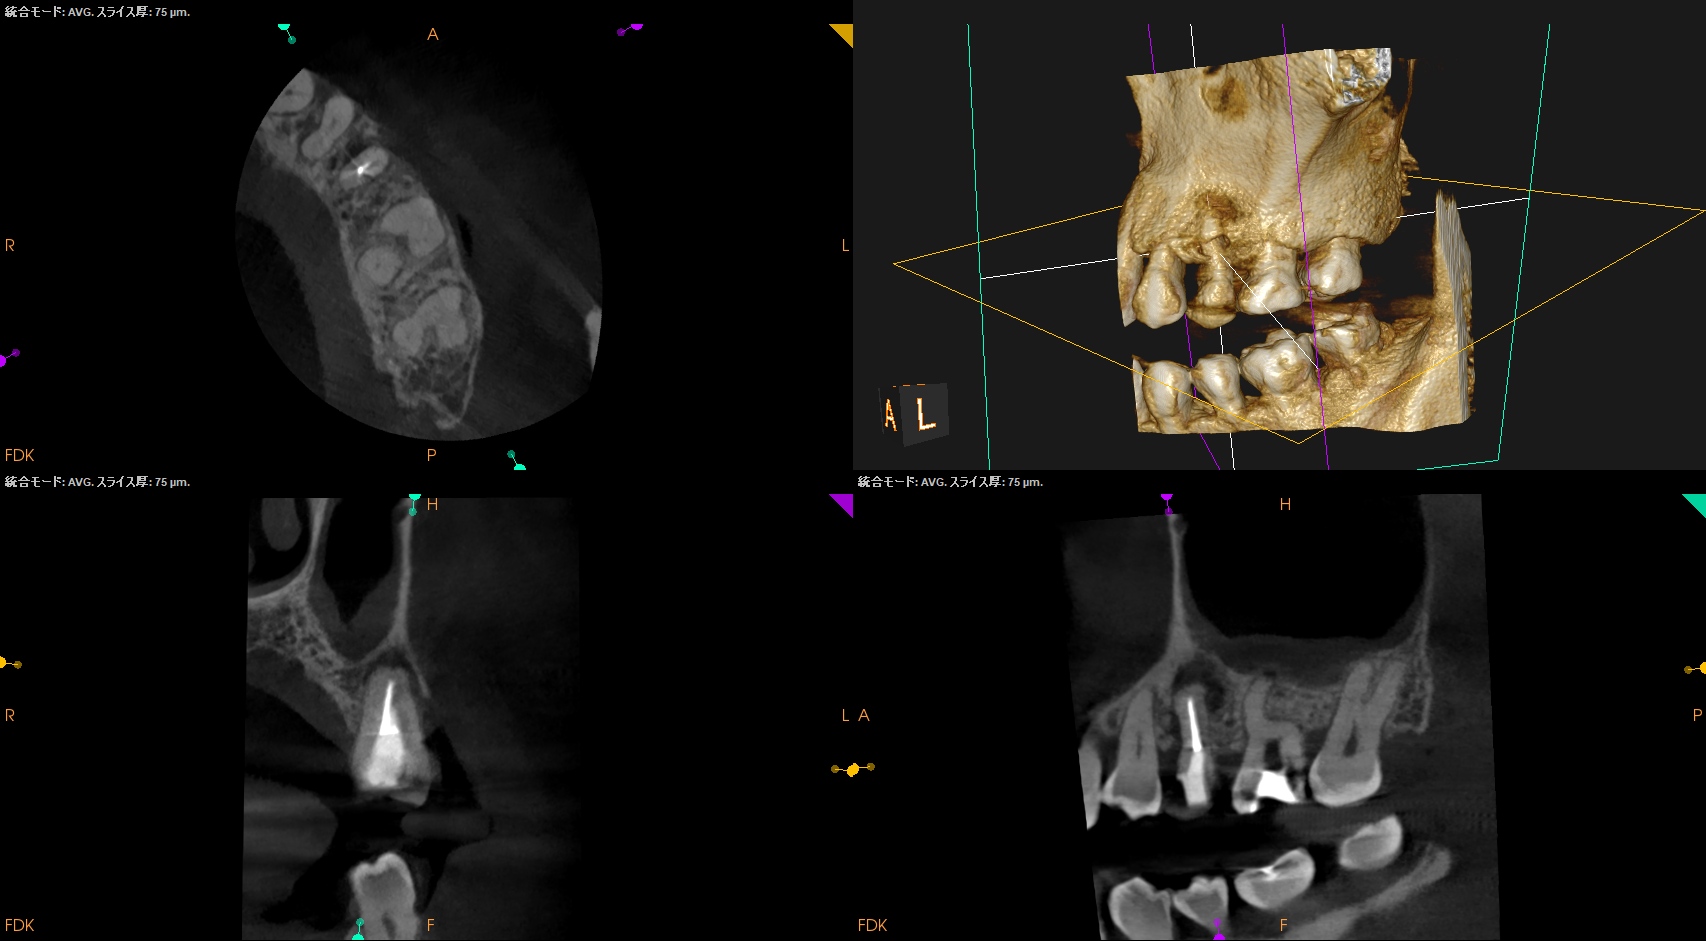

CBCTも撮影した。

これはマストの医療行為である、と私からは告げておこう。

さておき、#13にも病変があるのがわかるので#13も分析した。

#13

#13は#14よりも大きな根尖病変がある。

ここも治療が必要だろう。

Pulp Dx: Previously initiated therapy

Periapical Dx: Symptomatic apical periodontitis

Recomended Tx: Re-RCT

おおよその作業長が類推できる。

が、いずれにしてもこの治療での最大のポイントになるのはMB2がどこにあるか?である。

MB2の根尖部にはCBCTで根尖病変があるからだ。

作業長が術前に予測したCBCTでの作業長に近似していること

を。

これが、

CBCTの威力

である。